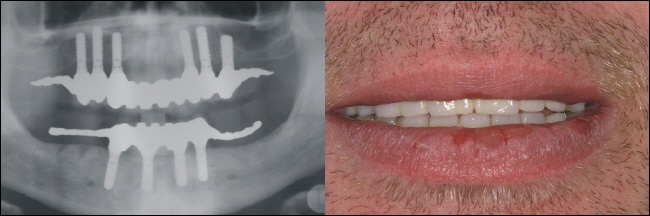

Das Bild rechts zeigt den zahnlosen Oberkiefer. Im Röntgenbild sieht dies aus wie auf dem linken Bild (gelber Kreise). |

Der zahnlose Unterkiefer rechts im Bild bietet keinen Halt mehr für eine Prothese. Links zeigt sich der zahnlose Knochenabschnitt im Röntgenbild (gelber Kreis). |